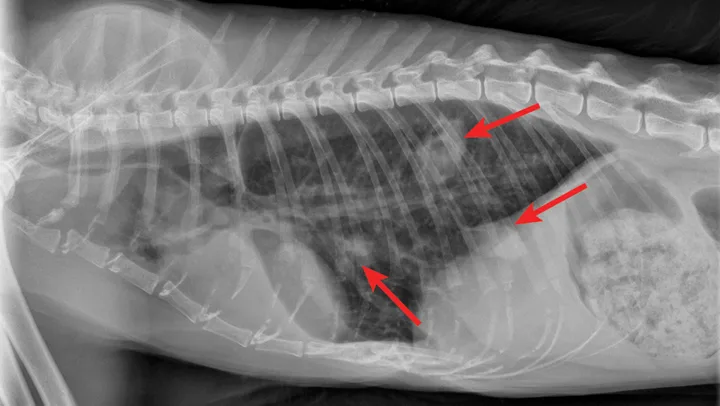

Radiographic evaluation is variable. Classic cranioventral distribution is less common in cats (Figure 3). A bronchial pattern is most common; however, bronchointerstitial, alveolar, and more structured pseudonodular patterns can occur.6,8 Occasionally, pulmonary abscesses may be appreciated and resemble pulmonary neoplasia (Figure 4).

FIGURE 3

Radiograph of bronchopneumonia with more classic cranioventral distribution (arrows). Other diseases, including CHF, have a similar distribution. Lack of this pattern does not rule out infection.